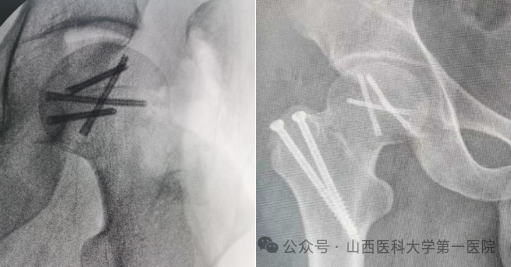

一位24岁的青年男性患者由于车祸导致罕见髋部损伤(右髋关节后脱位➕右股骨头骨折),入院后骨科主任杨自权高度重视,迅速组织术前准备,制定治疗策略,带领刘峰瑞副主任医师为患者进行了手术治疗,并取得良好手术效果。

外侧切口,外科脱位入路,显露可见游离股骨头骨块约1/4

精确解剖复位后2.5空心埋头钉固定,复位股骨头脱位及大转子截骨块

杨自权强调,对于股骨头骨折,既要精确对位,更要重视股骨头血运及髋关节肌群的保护,保护患者髋关节,避免股骨头坏死,外科脱位入路是治疗复杂股骨头骨折的金标准术式,属于保髋入路。它通过科学的解剖设计和“大转子翻转截骨”技术,完美地解决了手术显露与血供保护之间的矛盾,可以安全地将股骨头脱出髋臼、360度无死角地显露股骨头和髋臼的方法,同时保留了股骨头的主要血供,从而极大降低了术后股骨头坏死的风险,为患者获得良好功能预后提供了保障。既往传统入路破坏髋关节血运,往往造成股骨头坏死,这项技术需要术者具备扎实的髋关节外科解剖知识和精湛的手术技巧。